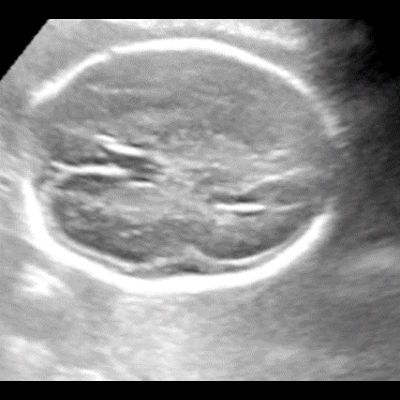

- A) USG incelemede serebral kortikal yapılar düzleşmiş (ok), gyrus sayısı azalmıştır (ok). Kalın ve ekojenik korteks mevcut olup korteks -beyaz cevher ayrımı silik görünümdedir. Posterior fossada ekstraaksiyel BOS mesafesi artmış görünümdedir (ok).